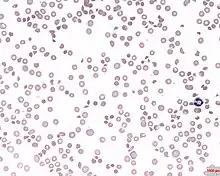

A photomicrograph of the blood showing thrombocytopenia

In hematology, thrombocytopenia is a condition characterized by abnormally low levels of platelets (also known as thrombocytes) in the blood.[2] Low levels of platelets in turn may lead to prolonged or excessive bleeding. It is the most common coagulation disorder among intensive care patients and is seen in a fifth of medical patients and a third of surgical patients.[3]